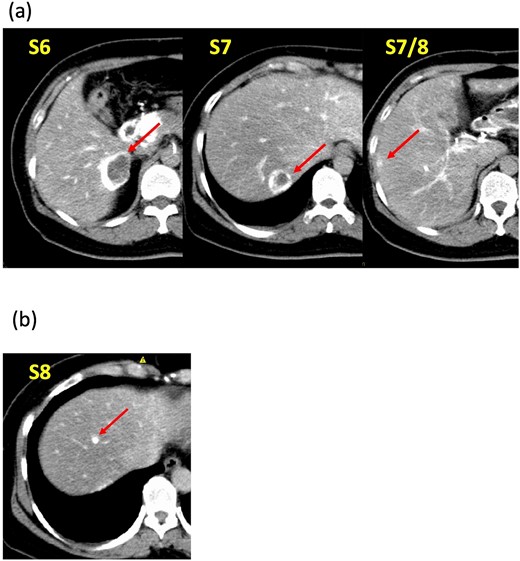

A 52-year-old woman was admitted to our hospital for the evaluation and treatment of multiple cystic liver tumors. Two years earlier, dynamic computed tomography (CT) had detected multiple cystic tumors in segments 6 (S6) and 7 (S7), which were subsequently monitored (Fig. 1a). The patient showed no symptoms; laboratory tests for tumor markers such as α-fetoprotein, protein induced by vitamin K absence or antagonist-II, carcinoembryonic antigen, and carbohydrate antigen 19–9 were within normal ranges. Dynamic CT identified two low-density tumors with peripheral enhancement in the portal phase, featuring cyst-like internal septa (Fig. 1b), which showed slow enlargement over 2 years. Magnetic resonance imaging (MRI) using gadoxetic acid (gadolinium-ethoxybenzyl-diethylenetriamine pentaacetic acid; EOB Primovist®) revealed that tumors appeared as low intensity signals on T1-weighted imaging and high intensity signals on T2-weighted imaging and diffusion-weighted imaging. Additionally, a 7-mm lesion was observed at the S7/8 boundary (Fig. 2a and b). Positron emission tomography-CT (PET-CT) showed abnormal uptake in S6 and S7 tumors but not in the S7/8 lesion (Fig. 3). CT during hepatic arteriography (CTHA) demonstrated well-contrasted tumors at the periphery, with no contrast enhancement in the center (Fig. 4a). Moreover, CTHA detected a new tumor in S8, displaying clear and uniform contrast but not visible with other imaging modalities (Fig. 4b).

Computed tomography during hepatic arteriography findings. (a) Known tumors in S6, S7, and S7/8 exhibit peripheral contrast enhancement but lack contrast in their centers. (b) The new tumor in S8 displays a distinct, uniform contrast effect.

Investigating NENs in the liver during the preoperative examination requires several diagnostic modalities. Common recommendations include contrast-enhanced CT, MRI, ultrasound, PET-CT, and somatostatin receptor scintigraphy, with the modality choice depending on the specific clinical situation. NENs often cause minimal symptoms and are frequently discovered incidentally on CT. Although many NENs are characterized by hypervascularity, those with higher malignancy levels may exhibit reduced vascular density and contrast enhancement, occasionally appearing as cystic lesions [7]. MRI is considered more effective than CT for detecting lesions [8]. The high diagnostic potential of EOB-MRI for liver tumors is recognized and considered an alternative to the invasive CTHA and CT arterial portography [9]. However, the S8 lesion herein was only delineated by CTHA. CTHA appears to enhance the accuracy of hypervascularized tumor detection by imaging immediately after selective hepatic-artery contrast administration. In this case, CTHA showed contrast at tumor margins but none at the center, indicating necrosis. The smaller lesion in S8 had not yet developed central necrosis and displayed only contrast on CTHA. Owing to tumor delineation by preoperative CTHA, we could resect it with no residuals. Furthermore, the patient has been recurrence-free for 3 years post-surgery. Thus, CTHA may be particularly useful for PHNET.